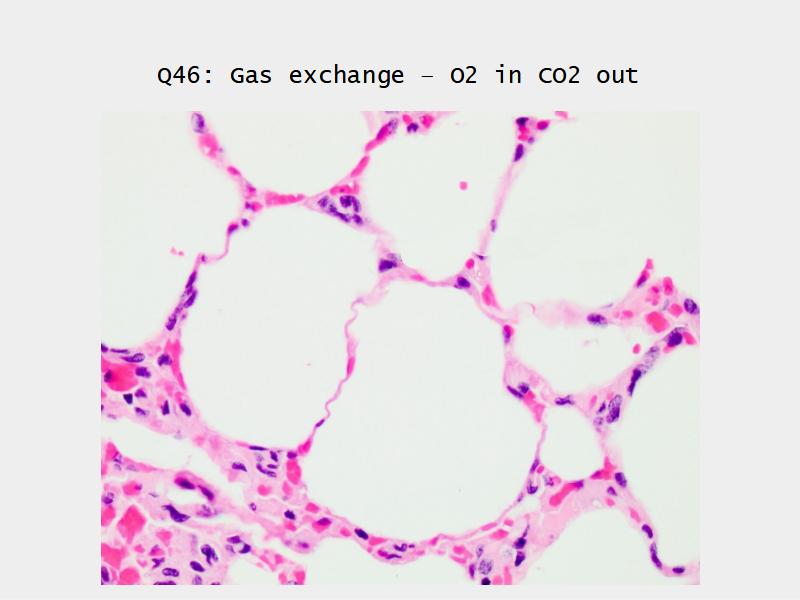

What cells are present?

Components of the Blood-Air Barrier?

- Alveoli